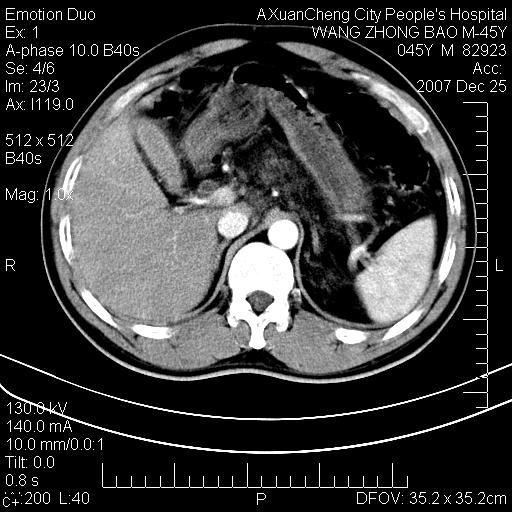

以下是引用qiuleiyu在2007-12-25 18:14:00的发言:[br]胰腺增大,周边渗出改变,肾前筋膜明显增厚,示少量积液.胆囊壁毛糙,周边少许渗出,胆总管壁厚,异常强化,然扩张不明显.结合病程急短;考虑;胆管炎,胆囊炎,胆源性胰腺炎可能大,请结合实验室检查及随访.

以下是引用lisihao在2007-12-25 14:23:00的发言:[br]急性水肿型胰腺炎[br]依据:1、胰腺弥漫性肿大,边缘稍毛糙;[br] 2、双侧肾周筋膜增厚,尤以左侧为甚(重要征象)[br] 3、双侧后胸膜增厚(刺激性炎症);[br] 4、结合病史,查血尿淀粉酶应该可以确诊。